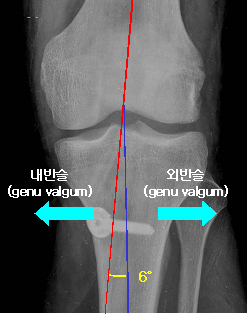

1) 하지의 정열

- 내반슬(genu varus) : O자 다리 - 양 발목 사이가 9-10cm 이상

- 외반슬(genu valgum) : X자 다리 - 양 슬관절 사이가 4cm 이상

- 경대퇴골간 각(tibiofemoral shaft angle) : 6도